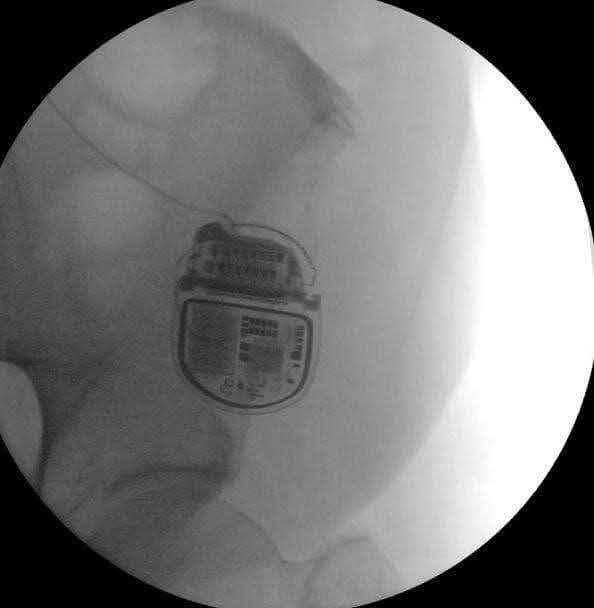

يتم زراعة النظام بالكامل داخل الجسم حيث يكون الجهاز تحت الجلد وتوضع الأقطاب الكهربية داخل العمود الفقري. ان الجهاز الجديد الذي زُرع في شيبا، للمرة الأولى في إسرائيل، فهو جهاز "ذكي" تم تطويره من قبل شركة ميدترونيك.

ما الذي يميز الجهاز الجديد؟ يتضمن الجهاز الجديد تكنولوجيا متقدمة تعتمد على آلية "الدائرة المغلقة". وقد تم زرعه في مريض استنفد جميع العلاجات الدوائية والتدخلات دون أن يكون قادرًا على المشي بدون مساعدة أو أداء الأنشطة اليومية مثل الانحناء، ربط الحذاء، الوقوف لفترات طويلة، وغيرها.